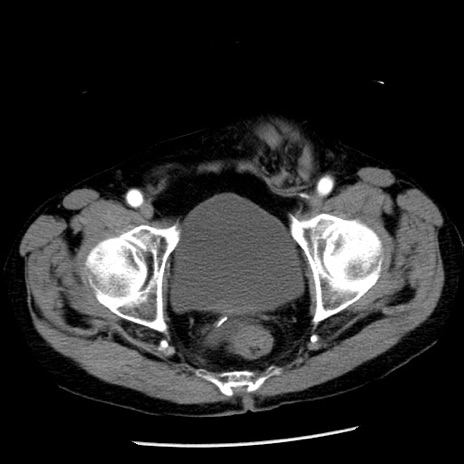

症例26(横断像)

【症例】80歳代男性

【主訴】嘔吐

【現病歴】昨晩2回嘔吐あり、今朝になっても嘔吐あり。来院。

【既往歴】胃潰瘍

【身体所見】意識清明、BT 37.6℃、BP 166/95mmHg、HR 100bpm、SpO2 97%、腹部:平坦・軟、腸蠕動音聴取良好、圧痛なし。

【データ】WBC 21900、CRP 1.46